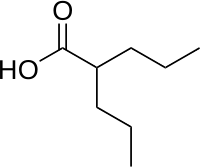

| Formula | C8H16O2 |

| Molar mass | 144.211 g·mol−1 |

Valproate's precise mechanism of action is unclear.[1][5] Proposed mechanisms include affecting GABA levels, blocking voltage-gated sodium channels, and inhibiting histone deacetylases.[6][7] Valproic acid is a branched short-chain fatty acid (SCFA) made from valeric acid.[6]

Valproic acid is a branched short-chain fatty acid and a derivative of valeric acid.[6]